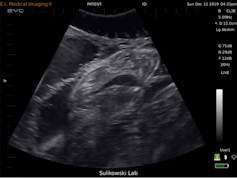

Just like the ultrasounds used on humans, we use a mobile ultrasound machine to figure out if a shark is expecting. I put on a pair of goggles that allow me to see everything the ultrasound sees, lean over the side of the boat, and place the probe onto the upside down shark’s abdomen. The image is usually fuzzy at first as water splashes over the shark and up onto the boat. The team holds the shark still as I slowly maneuver the probe along her belly. Then, if she’s pregnant, something magical happens.

Wriggling baby tiger sharks, up to 40 of them packed tightly together inside their mother’s womb, appear in front of my eyes. The image also appears on a screen held by another team member on the boat, and everyone cheers as they gather around to take a peek into the secret world of unborn sharks. We spy on them as they pump fluid through their still-developing gills, and we watch in awe as they wiggle around, blissfully unaware that anything extraordinary is happening outside in the world. Once we have enough data on the approximate size of the offspring – which gives us an idea of how far along the pregnancy is – it’s time to tag the mama shark.

As I hold the probe as still as possible to keep a visual of the shark’s internal anatomy, Dr. Sulikowski takes the Birth-Tag and uses a custom-designed applicator to carefully insert it into the uterus through the urogenital opening. No surgery required, the tagging procedure is complete in a matter of minutes. Once the tag is inside the uterus, we rotate the shark upright to wake her and release her back to the open ocean. I am filled with hope as I watch her swim gracefully away to continue her pregnancy, with a stow-away Birth-Tag hidden among her unborn offspring.